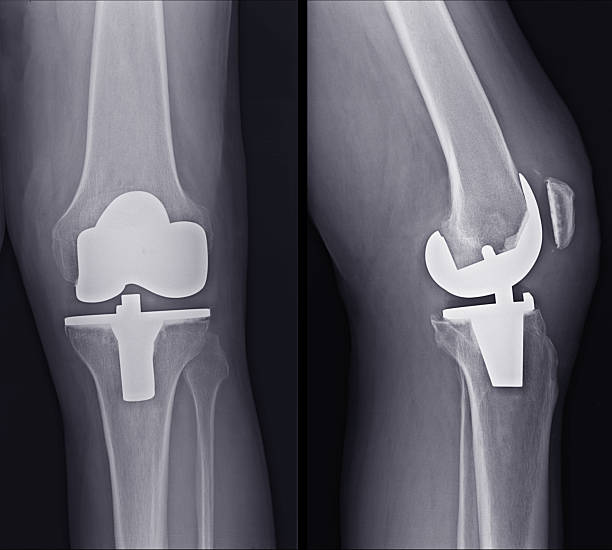

Total knee replacement, also known as total knee arthroplasty, is a surgical procedure designed to relieve pain and restore function in severely diseased knee joints. This procedure is typically recommended for patients suffering from severe arthritis or significant knee injuries that have not responded to conservative treatments such as medications, physical therapy, or less invasive surgeries. The knee joint, which is the largest joint in the body, is composed of the lower end of the thighbone (femur), the upper end of the shinbone (tibia), and the kneecap (patella). In a healthy knee, these bones are cushioned by cartilage, which allows for smooth and pain-free movement. However, in cases of severe arthritis, this cartilage wears away, leading to bone-on-bone contact, pain, and reduced mobility.

During a total knee replacement surgery, the damaged bone and cartilage are removed from the knee joint and replaced with artificial components. These components typically include a metal femoral component, a metal and plastic tibial component, and a plastic patellar component. The artificial parts are designed to mimic the natural movement of the knee, allowing for improved function and reduced pain. The surgery involves making an incision over the knee, removing the damaged tissue, and securing the new components to the bone using specialized cement or other fixation methods.

Partial and total knee replacements are surgical procedures designed to alleviate pain and restore function in patients with severe knee arthritis, but they differ significantly in their approach and scope. This procedure is less invasive, preserving more of the patient's natural knee structures, including the ligaments. In contrast, total knee replacement involves replacing all three compartments of the knee: the medial, lateral, and patellofemoral (front) compartments. This procedure is recommended for patients with widespread arthritis affecting the entire knee joint. During the surgery, the damaged bone and cartilage are removed and replaced with metal and plastic components designed to mimic the natural movement of the knee.